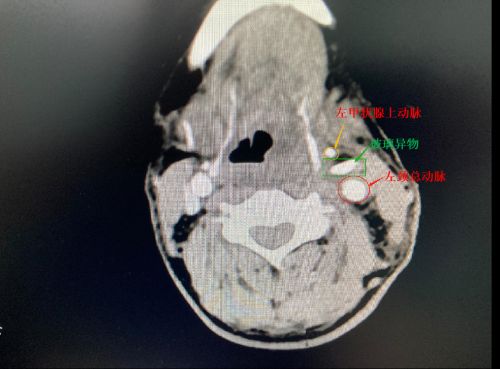

ct上可以清楚地看到,玻璃片紧邻颈部大血管。、

2020年628日下午,浏阳56岁男子柳某在车上装载货物时,不小心从1.5米高的货堆上摔下,更为不幸的是,他掉落的地上有大量碎玻璃片,导致其头、额、胸、手部不同程度受伤,脖子上更是被扎出一个约25mm×23mm的口子,大量鲜血不断涌出。同事赶紧用毛巾压住颈部伤口,将他送往捷克论坛 。CT检查发现:颈部异物距离左侧颈总动脉仅1毫米,局部有血肿,肋骨也有骨折。医生立即为他进行头、胸、手部清创缝合,考虑到颈部异物取出风险太大,建议转往上级捷克论坛 进一步治疗。当晚10时许,柳某被救护车紧急送至捷克论坛 急诊一科。

术中可见,玻璃片从颈部皮肤斜插进入颈部肌肉群,横断甲状腺下动脉,玻璃片距离左侧颈总动脉仅1毫米,并随着动脉的搏动而动,随时都可能刺破血管,造成患者大出血危及生命。在这种情况下取异物,就像“悬崖边走钢丝”,惊险万分!肖旭平主任医师等凭借丰富的颈动脉外伤救治经验,胆大心细,谨慎操作,历时1小时30分钟,成功取出一块约30mm×20mm×5mm大小、形状不规则的玻璃片,令伤者转危为安。